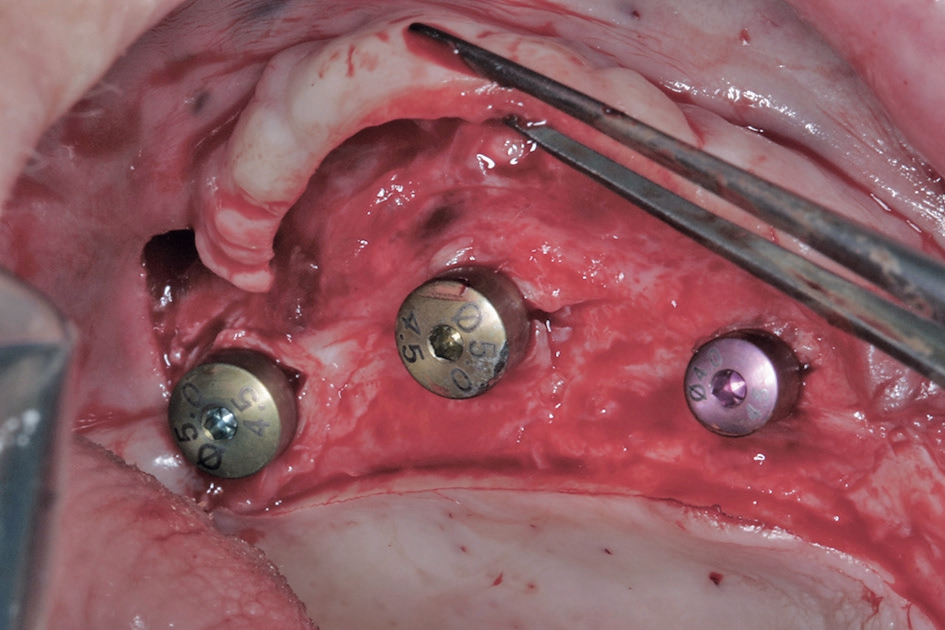

Vor dem zweiten OP-Eingriff nach 4 Monaten wurde im Labor eine Bohrschablone angefertigt. Zudem wurde ein DVT angefertigt, um im Sinne eines Backward planning die ideale Implantatposition planen zu können. Bei Eröffnung des augmentierten Kieferbereiches zeigte sich im augmentierten Bereich eine gute Regeneration und Revaskularisierung des Knochens (Abb. 14 bis 17). Sechs Implantate konnten somit in den augmentierten Bereich (Astratech EV®, DENTSPLY Sirona, Mannheim) mit ausreichender Länge und Durchmesser in Form einer gleichmäßigen Pfeilerverteilung in den Kieferknochen Inseriert werden (Abb. 18).